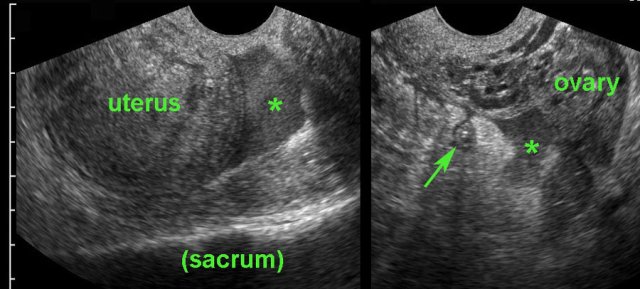

case 4

This functional, hemorrhagic cyst was a coincidental

finding and could easily be compressed against the promontory (p).

Complete resolution of the abnormalities within two weeks.